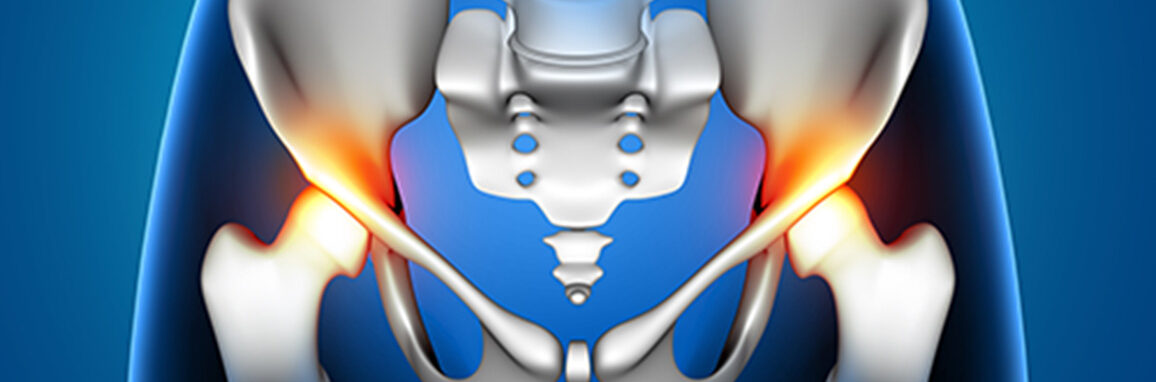

The hip joint is the pivot point for your body’s movement. When it is damaged by severe arthritis, ankylosing spondylitis, or AVN, simple actions like walking, sitting cross-legged, or getting out of a car become agonizing. At 206 Reasons Orthocare, our Total Hip Replacement protocol is designed to not just eliminate pain, but to restore your independence and gait.

Dr. Ruchit Shah performs Total Hip Replacement by removing the damaged “ball and socket” and replacing them with high-grade artificial components.

Stability Check: Intra-operative testing is done to ensure the hip is stable enough to allow for a full range of motion—crucial for patients who wish to sit comfortably or use Indian-style toilets (though we advise caution with extreme positions).

Diagnosis Matters: We distinguish between “hip pain” (groin) and “back pain” (buttock), which are often confused.